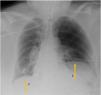

A 60-year-old patient with a history of emphysema who failed to wean from mechanical ventilation seven days after right-unilateral lung transplantation, an elevation of the left hemi-diaphragm was noticed (Fig. 1). To evaluate respiratory muscle mechanics transdiaphragmatic pressure (Pdi) was monitored during pressure support, revealing insufficient respiratory muscle strength showed in Pdi and ΔPgas/ΔPes ratio (Fig. 2, upper panel); as well in calculate partitioning pressure-time product (PTP) (Fig. 3). A remarkable biphasic morphology of Pdi during the inspiration was observed (Fig. 2, bottom panel), explained by the negative intrathoracic pressure drags the paretic and subsequent twitch of the competent hemi-diaphragm (arrows). This biphasic morphology of Pdi can distinguish hemi-diaphragm paralysis from other diaphragm dysfunction. The patient needs home ventilation.